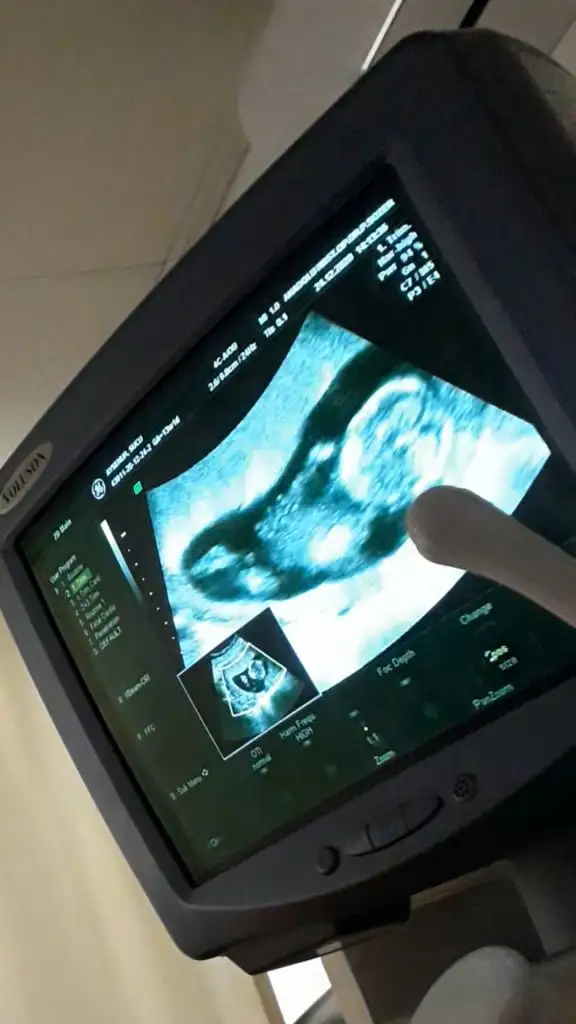

dr soylemeden siz gorun genital nub teorisi ( bebegin cinsiyeti)

Slm geçen hafta usg tahmininde kız demistiniz. Bugün doktorda kız gibi dedi. Pazartesiye fetal dna testini bekliyorum o zaman kesinleşecek 😍

Herkese selamlar, Ikra meyra Ikra meyra bana da yorum yapar mısın canım?

Ikra meyra Ikra meyra canım bana da yorum yapabilirsen çok sevinirim🤗

şu çıkıntı nubsa benim çok net sanki 😂

11+0 bu arada